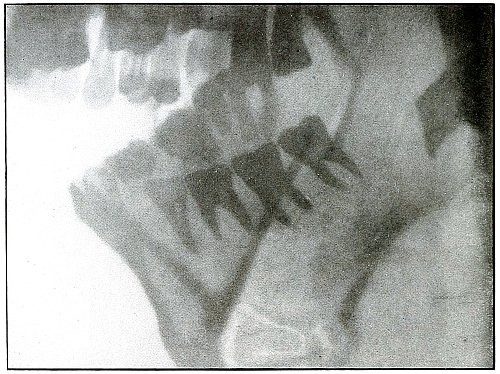

SPINAL REGION.

Plate 6.

[Pg 23]

Rifle—Plate 6.

SPINAL REGION.

Gunshot Wound of the Spinal Region—

Lodgment

of the Missile in the Lumbar Muscles.

The bullet is lodged deep in the muscles of the back and not in the

abdomen, as determined by inspection of the plate.

(a) The shadow of the bullet is enlarged laterally, because, while

on the side of the body next to the plate and to the spine, it is at

some little distance from the plate, which accounts for the larger

diameter of the shadow; and it is shortened longitudinally, because

its long axis is inclined at an angle to the plate.

(b) The outline of the shadow is distinct, an evidence that

it is extra-abdominal, as otherwise its outline would be blurred by

the diaphragmatic movement of respiration imparted to the abdominal

viscera during the Röntgen exposure.

[Pg 24]

Plate 7.

[Pg 25]

Rifle—Plate 7.

SPINAL REGION.

Gunshot Wound of the Spinal Region,

with Lodgment of the Missile.

The bullet was either dum-dummed or unjacketed because its soft nose

mushroomed, striking the crest of the ilium, penetrated the lumbar

muscles, and struck the side body of the third lumbar vertebra without

producing fracture.

The exposure, as the spinous processes show, was made with the spine

next to the plate, and the slight shadow, somewhat larger than the

projectile—to judge the size from the undeformed diameter—shows

it to be anterior to the vertebra. The shadow is deep enough to indicate

the location fairly near to the plate, and, almost certainly, not in

the abdominal cavity, where the distance from the plate would have

made the shadow less dense and the movement of respiration probably

would have given it a blurred outline. The shadow of the localizing

cross gives a standard of density to be compared with the shadow of

the projectile in making the estimation.

The treatment is conservative; only pain, paralysis, impaired

function, or sepsis indicate interference.

[Pg 26]